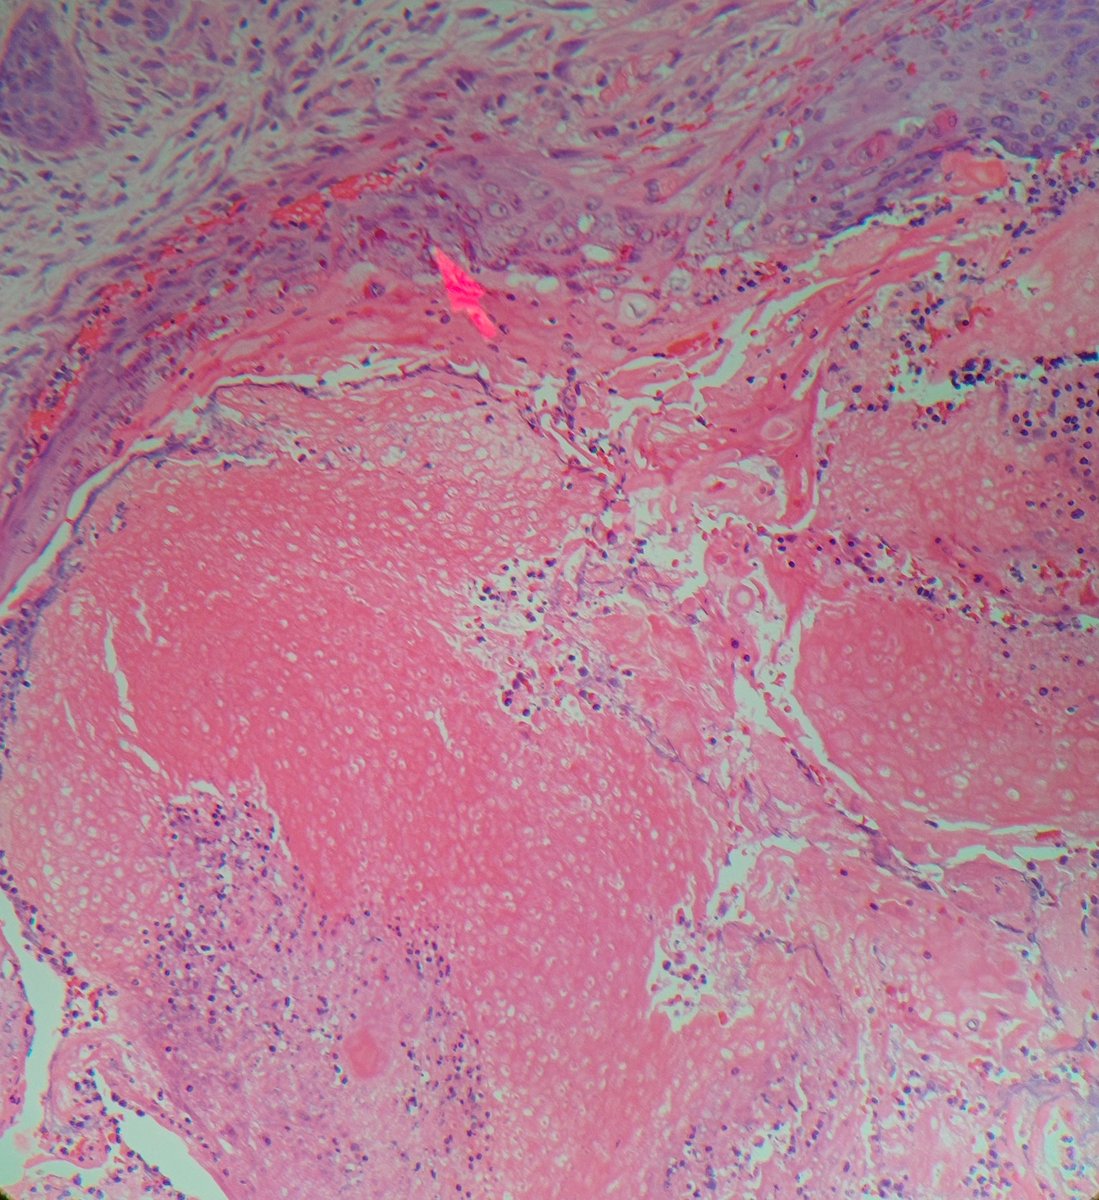

Nomenclature and histopath features of follicular tumors can get hairy, but let Dermnemonics help you! A special thanks to Drs. Edward Fulton and @JMGardnerMD who wrote the paper used as a reference! Benign follicular tumors (part 1) youtu.be/Wc6NFX6oS1U via @YouTube

YouTube video

YouTube